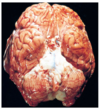

describe the etiology of a pale/bland infarct in the condition seen in the image

thrombotic/ischemic stroke: HTN → atherosclerosis → unstable plaque → thrombosis → **bland infarct**

describe the etiology of a red infarct in the condition seen in the image

embolic stroke atrial fibrillation + mural thrombus in left heart → legs (DVT) or BRAIN (red infarct)

the most commonly affected vessel in the condition seen in the image is the \_\_\_\_

the most commonly affected vessel in the condition seen in the image is the **middle cerebral artery**

describe the appearance of the brain seen in the condition in the image: early stroke: \_\_\_\_ old stroke: \_\_\_\_

early stroke: **red infarct** old stroke: **gliosis, scarring**

in the condition seen in the image, ____ is seen during 12-24 hours

in the condition seen in the image, **coagulative necrosis** is seen during 12-24 hours

in the condition seen in the image, \<24 hours is considered ____ while \>24 hours is considered \_\_\_\_\_

in the condition seen in the image, \<24 hours is considered **TIA** while \>24 hours is considered **stroke (permanent neurological deficit)**

in the condition seen in the image, ____ is seen after \>48 hours

in the condition seen in the image, **microglia → liquefactive necrosis** is seen after \>48 hours

in the condition seen in the image, ____ is seen after 2 weeks

in the condition seen in the image, **astrocytes → gliosis** is seen after 2 weeks

the condition seen in the image can be caused by long-standing _____ causing ____ which leads to _____ aneurysm

the condition seen in the image can be caused by long-standing **benign HTN** causing **hyaline arteriosclerosis** which leads to **Charcot Bouchard** **aneurysm**​

describe the 2 types of infarcts that HTN can lead to the condition seen in the image

* **slit hemorrhages** * hemorrhages thought to be secondary to microaneurysm rupture (Charcot Bouchard aneurysm) * **lacunar infarcts** * bland infarcts, thought to be secondary to thrombosis of a vessel w/ arteriosclerotic changes

describe the 4 types of vascular malformations that can lead to the condition seen in the image

* arterio-venous malformation = greatest potential for hemorrhage * cavernous hemangiomas * capillary telangiectasias * venous angiomas

cerebral amyloid angiopathy is a disease in which the same amyloidogenic peptides seen in ____ accumulate in the walls of ____ and can lead to the condition seen in the image

cerebral amyloid angiopathy is a disease in which the same amyloidogenic peptides seen in **Alzheimer's** accumulate in the walls of **medium and small caliber meningeal and cortical vessels** and can lead to the condition seen in the image

the most common location for the condition seen in the image is \_\_\_\_

the most common location for the condition seen in the image is **the basal ganglia**